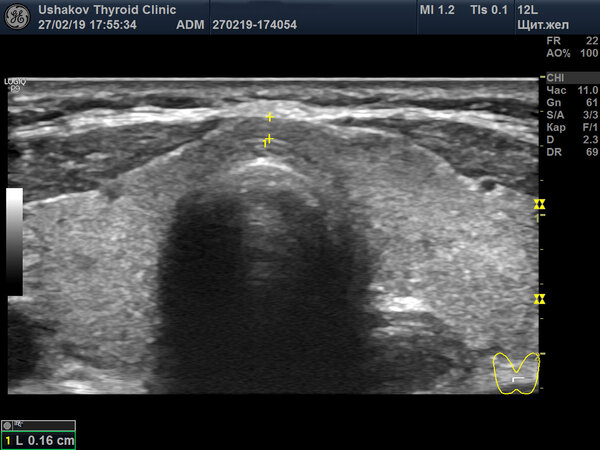

3. Измерение перешейка. Перешеек, соединяющий доли, обычно измеряют только по толщине (глубине). Если он утолщён неравномерно, могут быть замерены его правая и левая части отдельно.